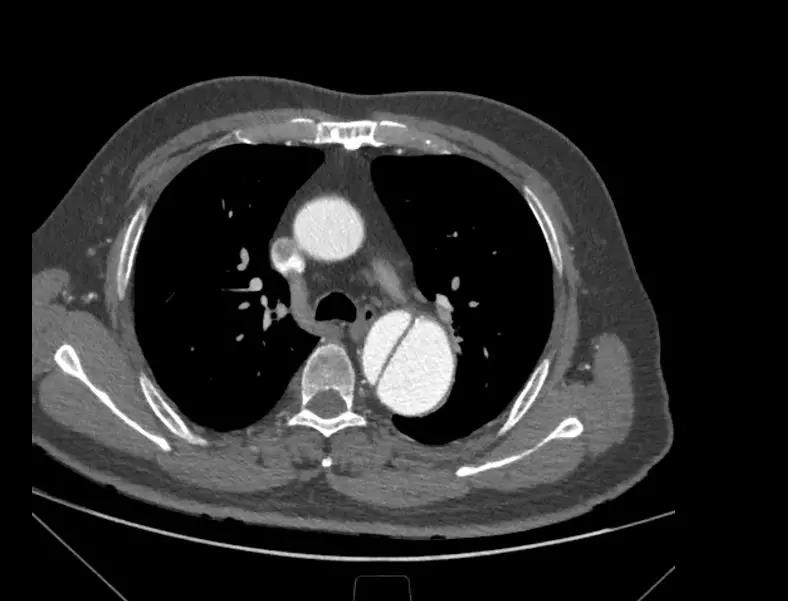

6月25日,中国医学科学院阜外医院向大会现场直播了一台采用先健新型主动脉支架系统进行的手术。手术由舒畅教授担任主要术者,接受手术的患者为一名65岁男性,入院后经CTA检查确诊为“慢性B型主动脉夹层”,夹层破口紧邻左锁骨下动脉,病变累及到两侧髂总动脉,主动脉真腔严重受压,假腔巨大,近端锚定区严重不足,病情十分危重。

经过测量和讨论,根据患者真腔受压严重、近端锚定区不足等特点,为了保留左锁骨下动脉,舒畅教授决定采用先健新型主动脉支架系统进行手术,该产品由Ankura™ Pro主动脉主体覆膜支架系统和Longuette™主动脉分支覆膜支架系统(即裙边支架)组成,其中Ankura ™ Pro 支架的径向支撑力比较大,适合慢性夹层病变,同时,其具有良好的柔顺性和多种锥度,对于急性和亚急性夹层患者也是非常好的选择。Longuette™裙边支架有较大的径向支撑力,保证支架在与主体支架配合使用时不被压塌;同时有极高的柔顺性,可顺应各种解剖形态的分支血管。其独特的设计对于累及弓上分支的主动脉夹层且病情紧急的患者具有明显优势。

术中通过DSA造影显示:主动脉夹层破口位于左锁骨下动脉近端,真腔压闭。舒畅教授通过左锁骨下动脉预置Longuette™裙边支架,释放 Ankura™ Pro主动脉主体覆膜支架,封堵破口后通过裙边支架显影点准确定位,释放裙边支架,凭借着舒畅教授精湛的手术操作和器械的优异性能,手术过程非常顺利,胸主动脉支架释放良好,患者的主动脉夹层破口封闭良好,左锁骨下动脉释放的裙边支架血流通畅,没有内漏发生。由于患者远端真腔较小,为了保证远端的血流,植入了一个cuff支架,造影显示远端真腔打开良好。

(图:术前造影)